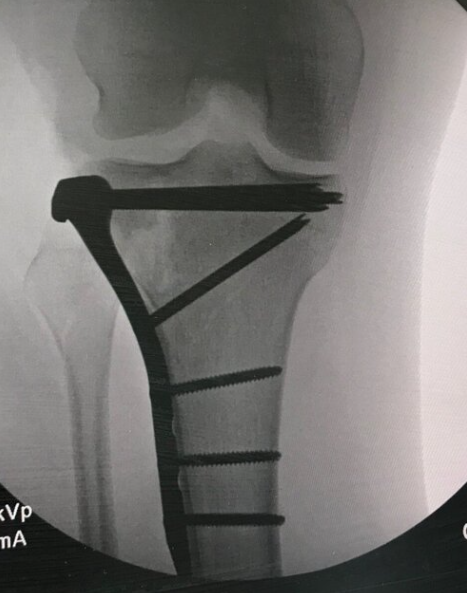

Here is a view of Emily’s repaired right knee after a bad mogul and then surgery in January 2020. She’s been a handful - LOL.